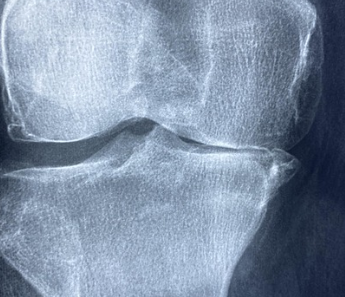

무릎 관절염이 의심될 경우, 병원에서는 여러 가지 검사와 문진을 통해 진단을 진행합니다. 일반적으로 사용하는 기본 검사는 X-ray 촬영이며, 이를 통해 관절 간격이 좁아졌는지, 연골이 얼마나 마모되었는지를 확인할 수 있습니다. 초기 관절염은 X-ray에서 큰 변화가 없을 수도 있어, MRI가 추가적으로 필요할 수 있습니다.

혈액검사 역시 관절염의 종류를 구분하는 데 사용되며, 특히 류마티스 관절염 여부를 감별하는 데 중요합니다. 염증수치(CRP, ESR)와 류마티스인자(RF), 항CCP항체 등의 결과를 통해 단순한 퇴행성 변화인지, 자가면역성 염증 질환인지 확인할 수 있습니다.

의사가 직접 무릎을 만져보며 관절의 움직임, 부기, 통증 부위를 확인하는 신체 진찰도 매우 중요합니다. 실제로 문진 과정에서 환자의 생활 패턴, 증상의 양상, 발병 시기 등을 종합적으로 파악하면 보다 정확한 진단이 가능해집니다. 무릎 관절염 초기 증상은 명확한 구조적 변화가 없더라도 임상 증상만으로 진단 가능할 수 있습니다.

조기에 진단을 받고 치료를 시작하면 진행 속도를 크게 늦출 수 있으며, 약물이나 물리치료 등으로도 큰 호전을 기대할 수 있습니다. 무릎 통증이 반복된다면 스스로 넘기지 말고 검사를 통해 현재 관절 상태를 확인해보는 것이 필요합니다.